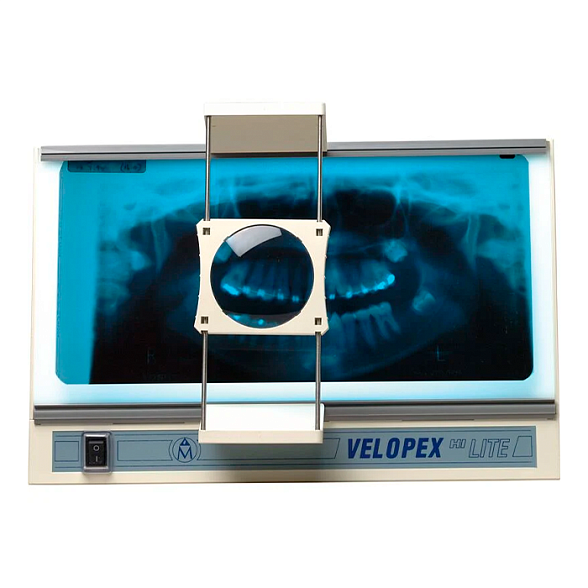

Daray DX4101LED Single Panel X-Ray Film Viewer - негатоскоп

Негатоскоп Daray DX4101LED: Профессиональная оценка рентгеновских снимков

Негатоскоп Daray DX4101LED — это современный и надежный просмотровый стол, предназначенный для точной и комфортной интерпретации рентгеновских, МРТ, КТ и других медицинских снимков. Он заменяет устаревшие люминесцентные модели, предлагая врачам-рентгенологам, травматологам, стоматологам и ветеринарам совершенный инструмент для ежедневной диагностической работы.

Однородная яркая LED-подсветка без мерцания и горячих точек обеспечивает идеальные условия для чтения даже самых плотных участков снимка, снижая нагрузку на зрение и минимизируя риск диагностических ошибок.

Ключевые преимущества для специалиста

Выбирая Daray DX4101LED, вы инвестируете в точность, эффективность и долговечность. Вот что делает этот негатоскоп оптимальным выбором для кабинета:

- Современная LED-технология: Светодиоды обеспечивают мгновенный выход на полную яркость, не требуют времени на прогрев и потребляют значительно меньше электроэнергии по сравнению с люминесцентными лампами.

- Равномерное освещение: Специальная рассеивающая панель создает однородный световой поток по всей площади экрана без темных углов или пересветов, что критически важно для корректной оценки плотности тканей.

- Регулировка яркости: Встроенный диммер позволяет плавно изменять интенсивность подсветки под конкретный тип пленки и индивидуальные предпочтения врача.

- Надежность и долгий срок службы: Светодиоды рассчитаны на десятки тысяч часов работы, что избавляет от частой и затратной замены ламп.

- Безопасность и экологичность: В конструкции не используются ртутьсодержащие лампы. Корпус выполнен из прочных, легко очищаемых материалов.

- Компактность и мобильность: Легкая и прочная конструкция позволяет легко перемещать негатоскоп между кабинетами или устанавливать его на столешницу, экономя пространство.

Области применения

Daray DX4101LED незаменим везде, где требуется детальный анализ медицинских изображений на пленке: в государственных и частных поликлиниках, больницах, травмпунктах, стоматологических центрах, ветеринарных клиниках, а также в научно-исследовательских учреждениях.

Технические характеристики Daray DX4101LED

| Параметр | Характеристика |

|---|---|

| Бренд / Производитель | Daray (Великобритания) |

| Модель | DX4101LED |

| Тип | Однопанельный негатоскоп (просмотровый стол) |

| Источник света | Светодиоды (LED) |

| Размер полезной области просмотра | 430 x 350 мм (подходит для стандартных снимков 35х43 см) |

| Габаритные размеры (Ш x В x Г) | Приблизительно 480 x 450 x 70 мм (требует уточнения) |

| Регулировка яркости | Да, плавная (диммер) |

| Цвет свечения | Холодный белый (стандартный для диагностики) |

| Яркость (приблизительно) | Высокая, > 4000 кд/м² (типичное значение для профессиональных LED-негатоскопов) |

| Питание | От сети 220-240 В, 50/60 Гц |

| Управление | Выключатель и регулятор яркости на корпусе |

| Крепление | Настольное. Возможность настенного монтажа с помощью дополнительного кронштейна. |

| Вес | Легкий, около 4-5 кг (требует уточнения) |

| Материал корпуса | Прочный пластик, металлические элементы |

Комплектация и эксплуатация

Негатоскоп поставляется готовым к работе. В стандартную комплектацию, как правило, входит сам прибор с блоком питания и сетевым кабелем. Установка элементарна: достаточно разместить его на ровной устойчивой поверхности и подключить к розетке. Уход заключается в периодическом протирании акрилового экрана мягкой тканью для удаления пыли и отпечатков.